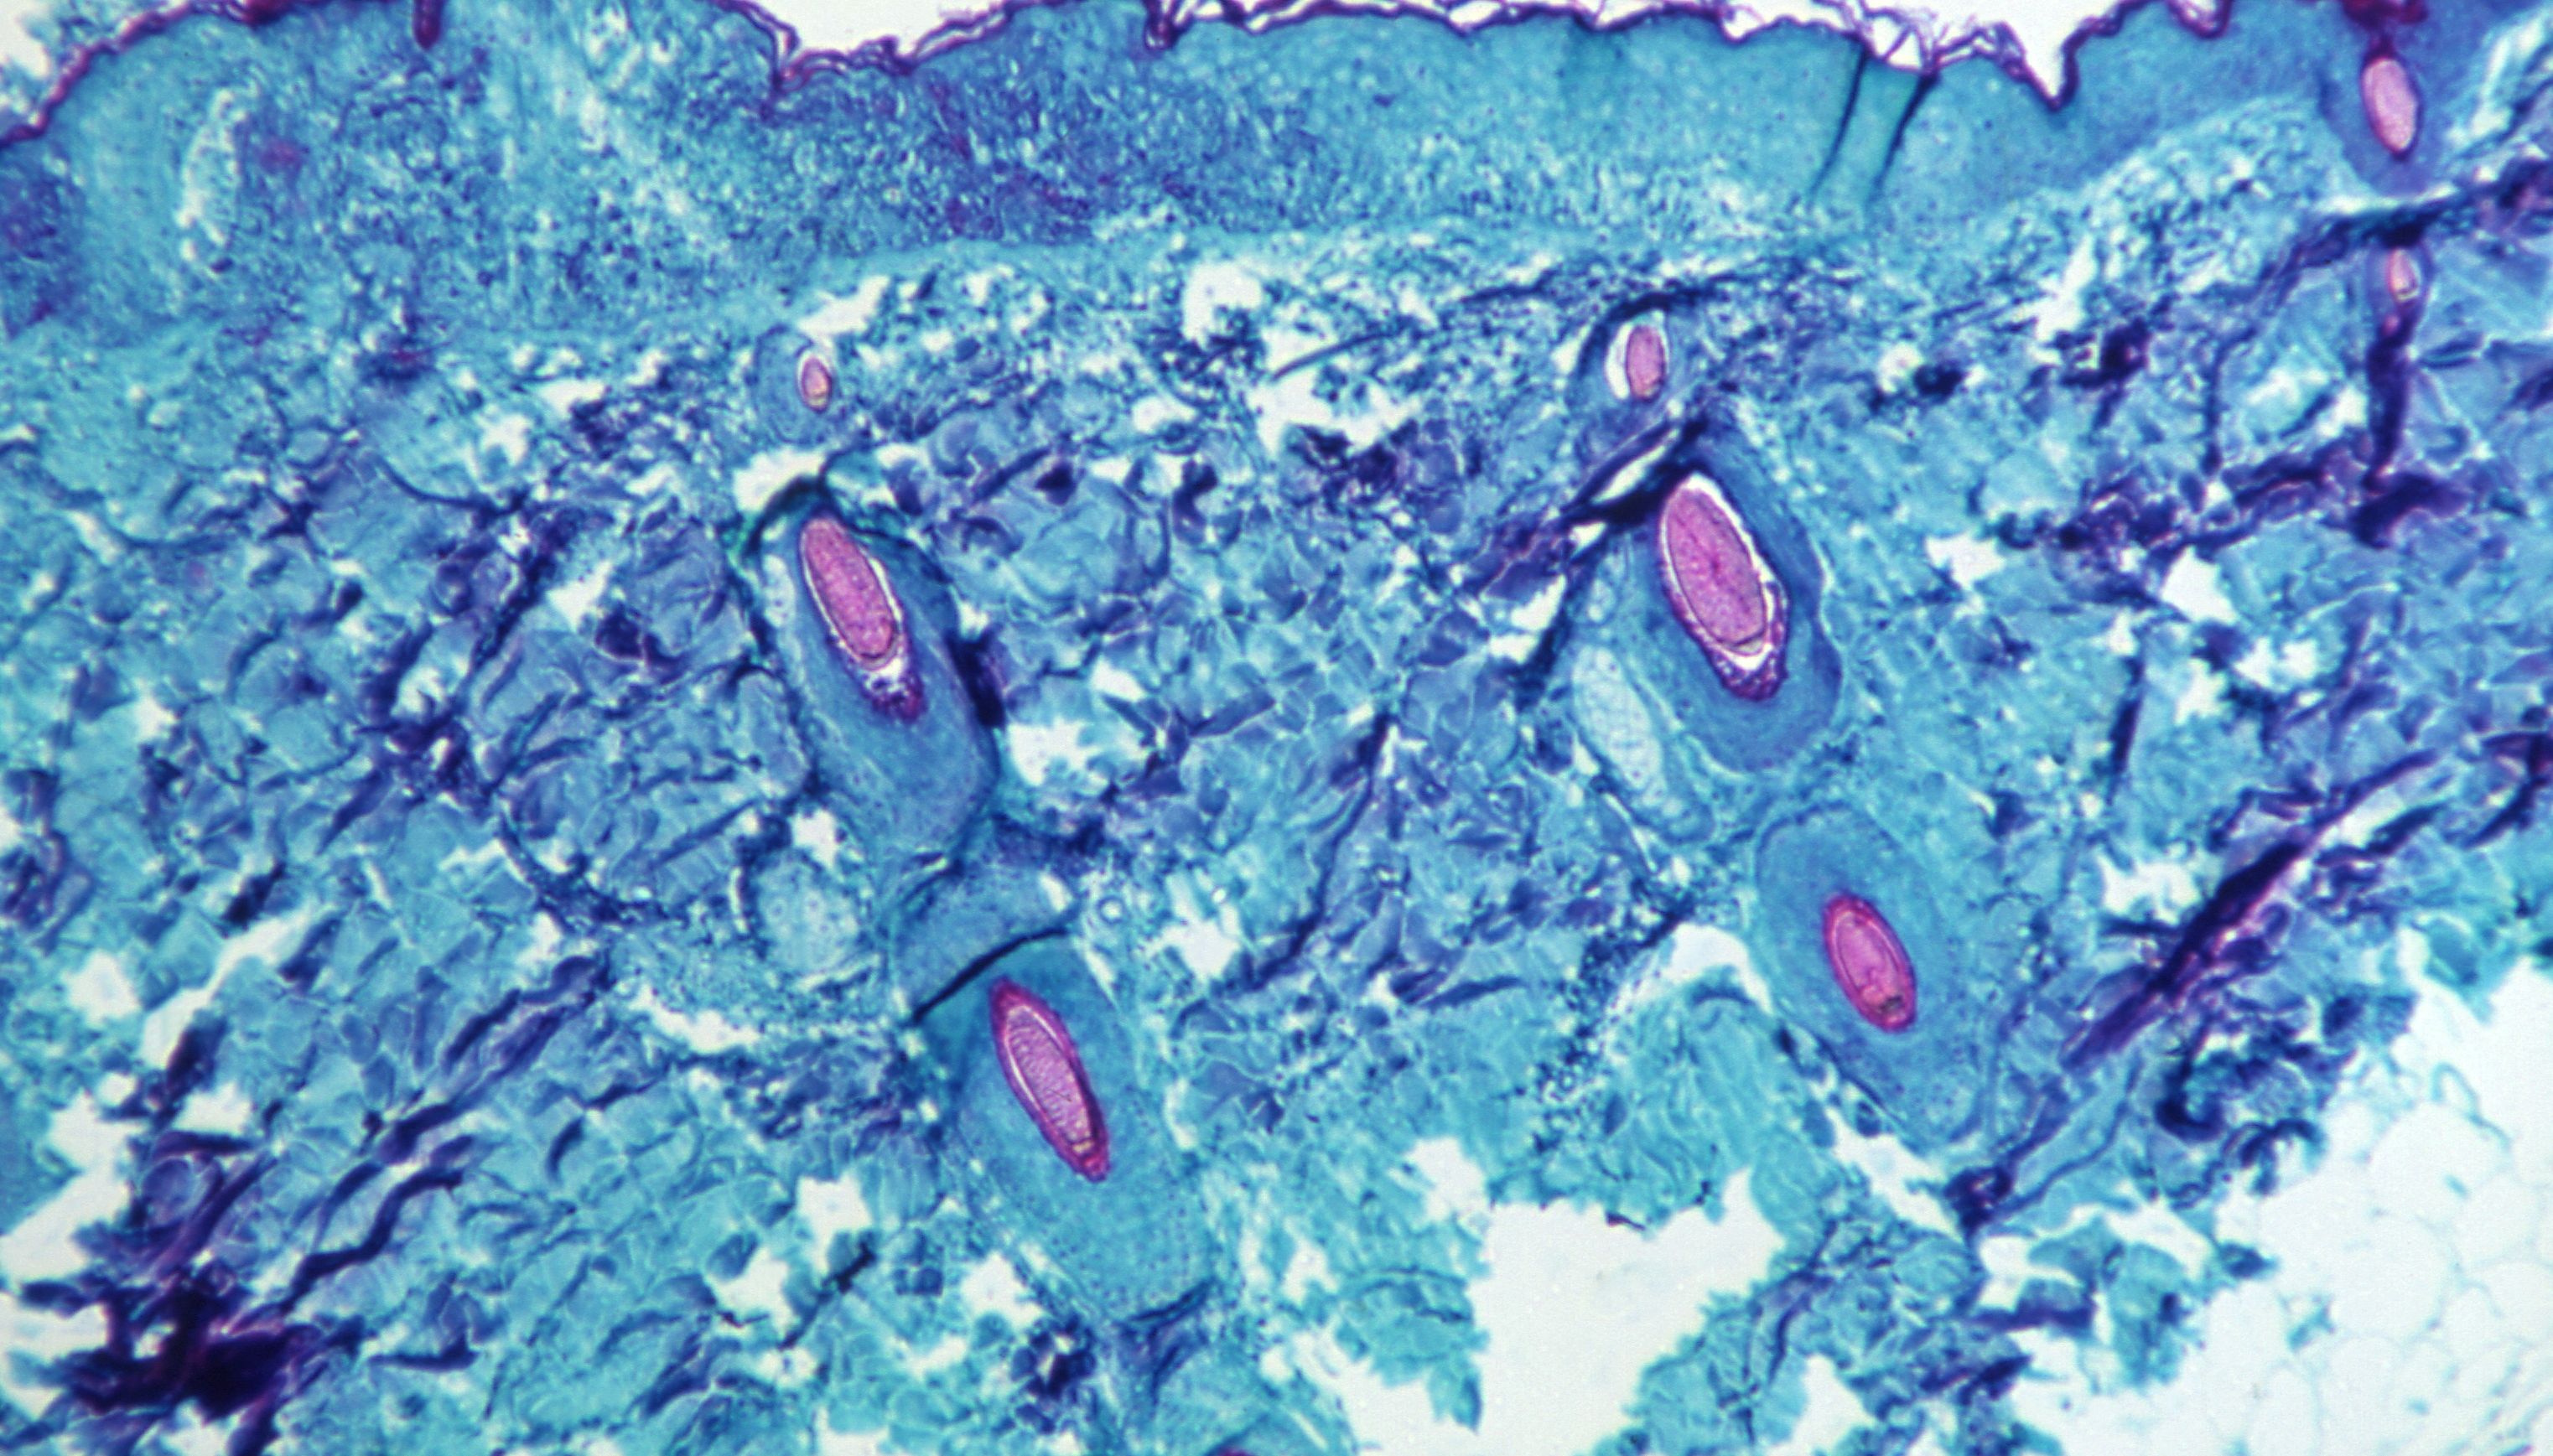

A section of skin tissue, harvested from a lesion on the skin of a monkey, that had been infected with monkeypox

CDC